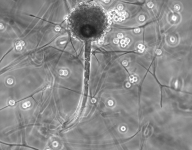

| Species Name: | Rhizopus microsporus var. microsporus |

| Taxonomy: | FUNGI Mucoromycota, Mucoromycetes, Mucorales, Rhizopodaceae |

| Substrate: | sputum, male 61 yr with chronic obstructive pulmonary disease and untreated diabetes | Location: | USA Massachusetts, Worcester (GEO: 42.263,-71.802) |

| Characters: | HUMAN/ ANIMAL PATHOGEN multifocal lung infection following brush clearing - Tsyrkunou AV, Ellison RT 3rd, Akalin A, Wiederhold N, Sutton DA, Lindner J, Fan H, Levitz SM, Zivna I, Med Mycol Case Rep. 8;6:14-7, 2014 (Click for publications citing UAMH 11833) |